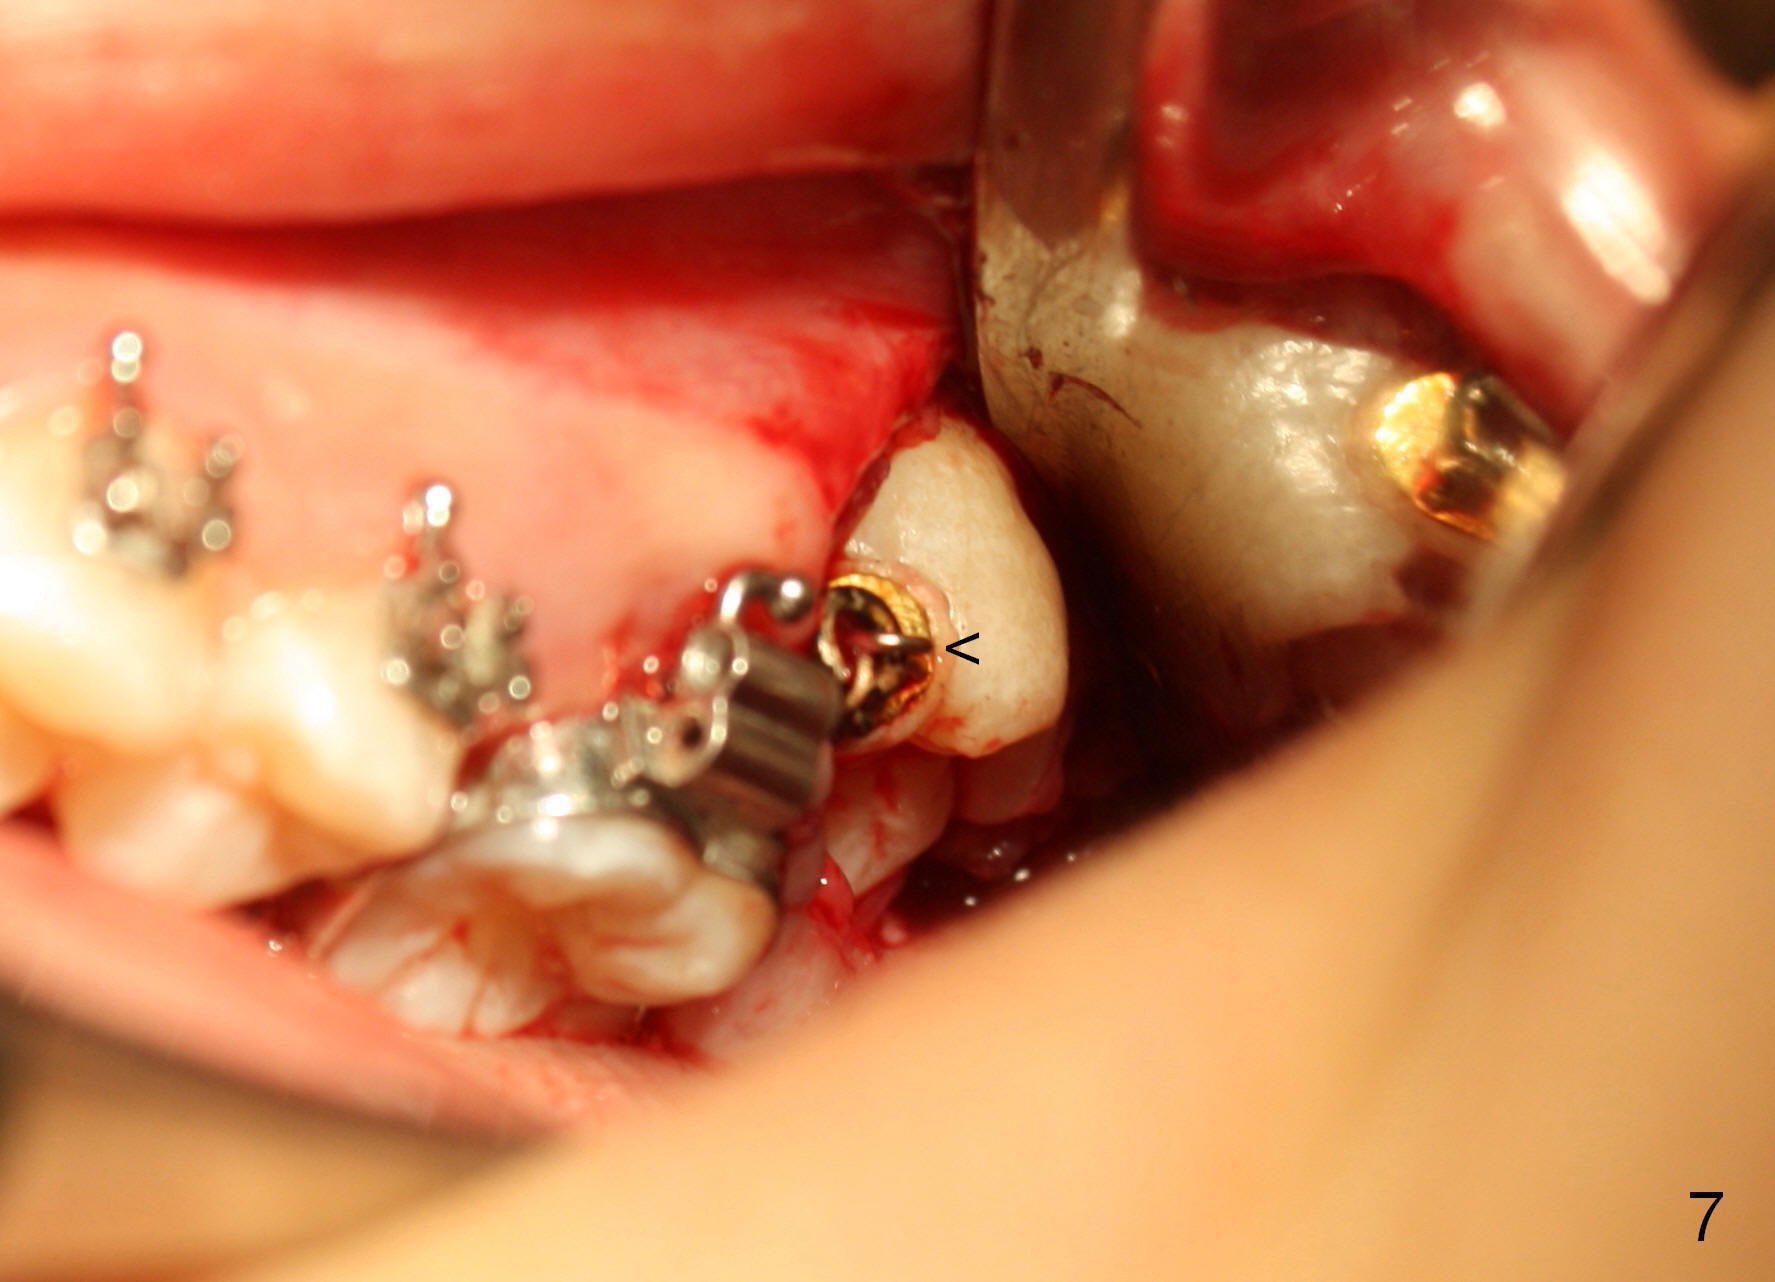

The distobuccal cusp of the tooth is subgingival 8 months post banding (Fig.6 (mirror view) *). A 2nd surgery is performed to expose the gold chain (Fig.7 <) and a bracket is placed. With arch wires, eruption of the impacted tooth is quickened (Fig.8). Later a 3rd minor surgery is done to place a lingual button to facilitate lingual cusp eruption. Finally a band has to be placed at #15. Treatment finishes in 2 years. The patient (15 years 2 months old) returns for follow up 3 months post debanding (Fig.9). There is no bone loss around the tooth #15 2 years 4 months post de-banding (Fig.11, as compared to the tooth #2 (Fig.10)).